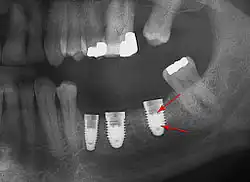

Установка зубных имплантатов может вести к периимплантиту, который возникает из-за бактериальной флоры, попадающей на внешнюю поверхность имплантатов через зубной налет. Лечение данного заболевания проводили корейские исследователи с использованием титановой щетки.

- с помощью рентгенографии изучаются качество и плотность костной ткани;